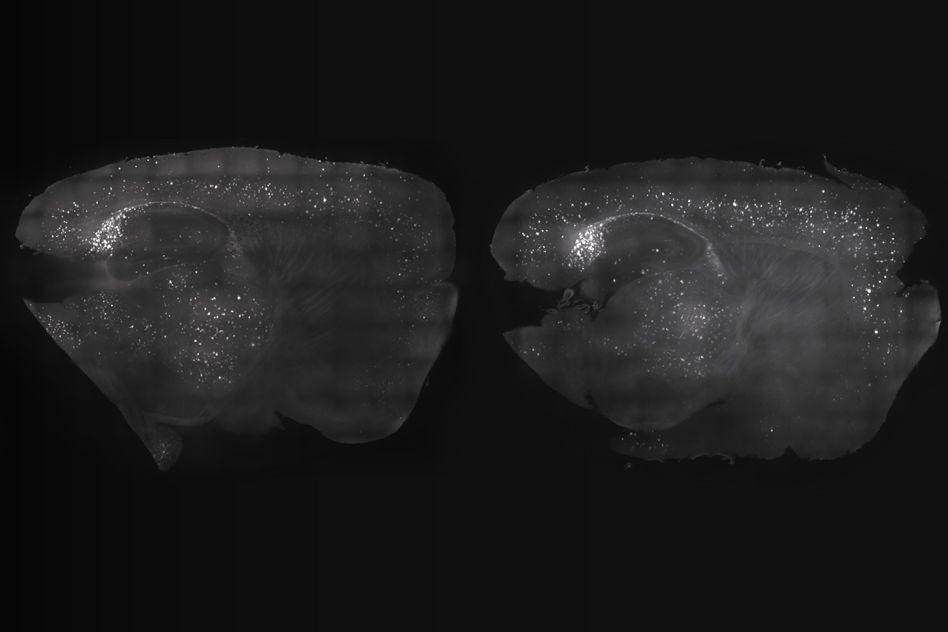

By exposing mice to a unique combination of light and sound, MIT neuroscientists have shown that they can improve cognitive and memory impairments similar to those seen in Alzheimer’s patients. At left, the mouse cortex shows a reduction in amyloid plaques following visual and auditory stimulation, compared to the untreated mouse at right.

By exposing mice to a unique combination of light and sound, MIT neuroscientists have shown that they can improve cognitive and memory impairments similar to those seen in Alzheimer’s patients.

This noninvasive treatment, which works by inducing brain waves known as gamma oscillations, also greatly reduced the number of amyloid plaques found in the brains of these mice. Plaques were cleared in large swaths of the brain, including areas critical for cognitive functions such as learning and memory.

The researchers then decided to try combining the visual and auditory stimulation, and to their surprise, they found that this dual treatment had an even greater effect than either one alone. Amyloid plaques were reduced throughout a much greater portion of the brain, including the prefrontal cortex, where higher cognitive functions take place. The microglia response was also much stronger.